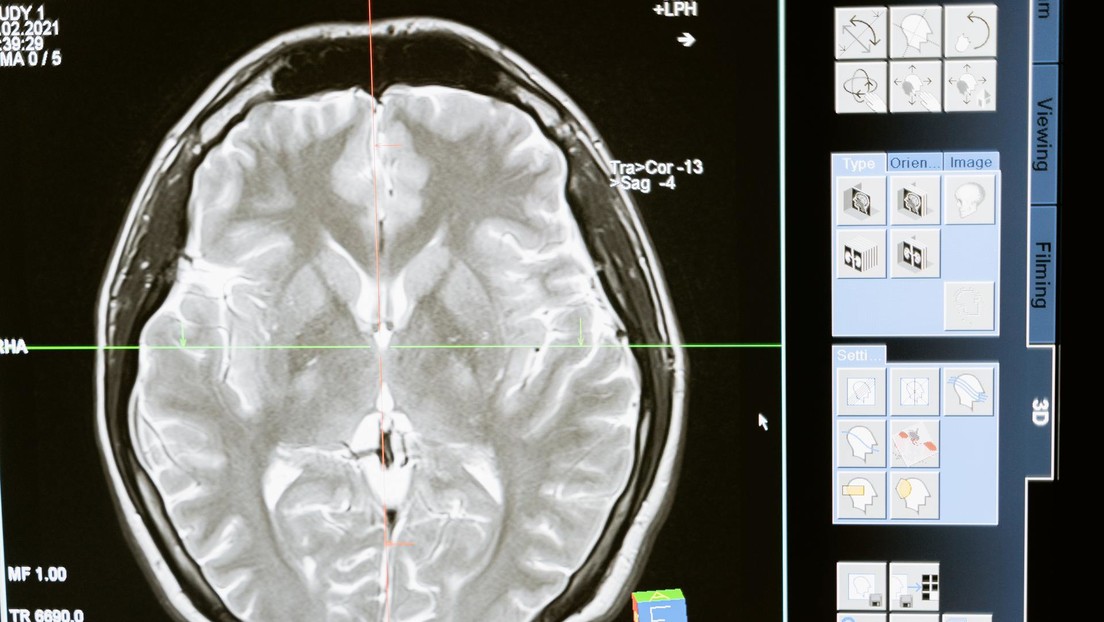

Samsung propone “copiar y pegar” la estructura del cerebro para crear chips neuromórficos – Alerta Digital